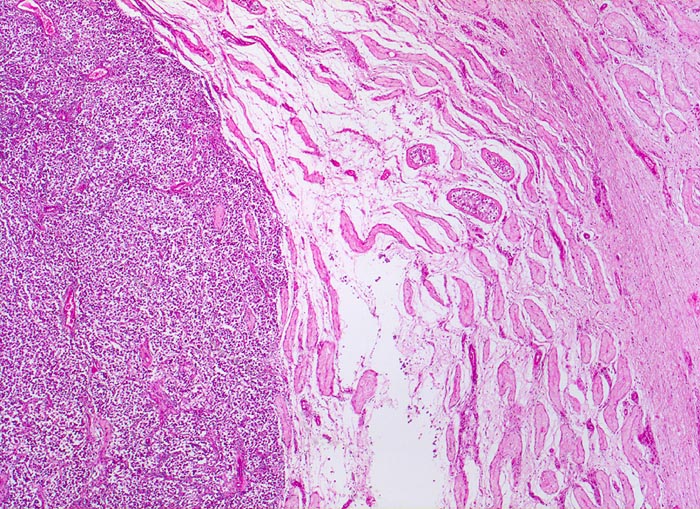

Makroskopisch imponieren Seminome als gut begrenzte weiche crèmefarbene Knoten oder diffuses Intiltrat. Mikroskopisch findet sich eine uniforme Population grosser Zellen mit prominentem zentralem Nukleolus, welche durch schmale Bindegewebssepten voneinander getrennte Nester bilden. Ein leukozytäres Entzündungsinfiltrat, synzytiotrophoblastäre Riesenzellen und Mikroverkalkungen können zusätzlich vorhanden sein. Gelegentlich induziert der Tumor eine ausgeprägte granulomatöse Entzündung. Dies kann zur Fehldiganose einer granulomatösen Orchitis führen.

Seminome entstehen aus einer Keimzellneoplasie in situ bzw. einem intratubulären Seminom mit sekundärer Invasion des Stromas (> 3082). Bei 75% der Patienten ist das Seminom bei Diagnosestellung lokalisiert. 15% haben aber bereits Metastasen in regionären retroperitonealen Lymphknoten oder viszerale Metastasen. In Einzelfällen ist der Primärtumor im Hoden trotz ausgedehnter Metastasierung nicht palpabel. Histologisch findet sich wenig oder gar kein Tumorgewebe und eine fibröse Narbe (sogenannter “ausgebrannter Hodentumor”) (> 3090).

• Unterschiedlich breite solide Tumorzellstränge aus monomorphen Zellen mit grossen hyperchromatischen Kernen und einem solitären zentralen prominenten Nukleolus. Reichlich helles Zytoplasma mit scharfen Zellgrenzen.

• Schmale bindegewebige Septen mit Kapillaren und lymphoplasmazellulärem Entzündungsinfiltrat.

• Tubuläre Atrophie des angrenzenden Hodenparenchyms. Einige Hodentubuli enthalten stark atypische pleomorphe Keimzellen (Keimzellneoplasie in situ).